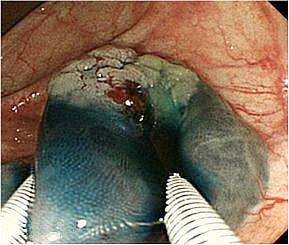

早期食道がん、胃がんを切らずに治す低侵襲な内視鏡治療

食道、胃における早期がんに対する内視鏡治療手技が発達し、根治ができる症例が増加

しており、従来の治療に代わる新しい治療法として注目されていますが、当院では可能

なかぎり食道、胃における早期がんに対しては内視鏡的粘膜下層剥離術(Endoscopic

submucosal dissection、以下ESD)を行っております。

ESD治療の実際

治療手技は内視鏡治療用の電気のメスで直接、病変部を切って剥ぎ取る方法です。高度

な内視鏡治療技術が要求されます。比較的大きな病変も一括切除が可能であるため局所

再発率を下げることや、顕微鏡による正確な病理診断を行い、がんの悪性度を正確に調

べることができることなどのメリットがあります。低侵襲治療と正確な病理診断を兼ね

た非常に優れた内視鏡的治療になりますが、しかし正確な病期診断が不可欠であり、早

期がんに対する各種画像検査を行い治療の適応を決定します。